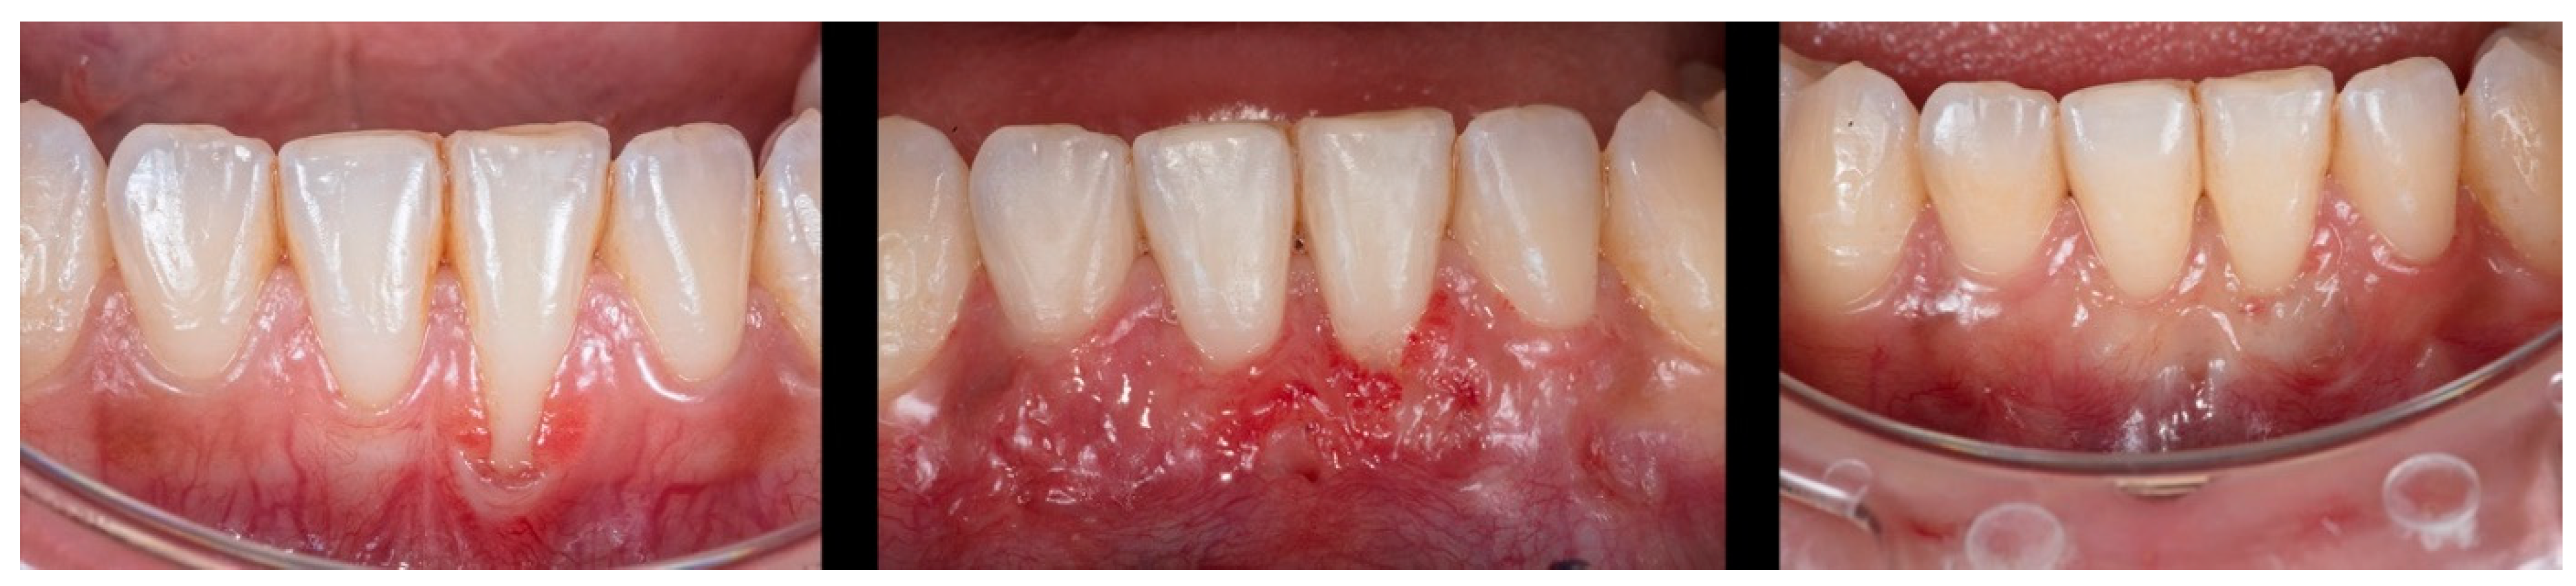

Figure 2.

Case 1 shows initial pictures of the GR defect (#41); immediate post-operative; and the healing period of 1 month and 6 months.

Case 1 was a male RT2 case involving tooth #41, with slight interproximal bone loss and gingival recession (GR) of 6mm (height) x 2.5mm (wide), which achieved the MGJ. No occlusal trauma was detected. The patient reported the use of fixed orthodontic brackets in the past. The MiTT protocol was entirely followed, and the suture was done with a composite in the buccal face of the teeth for coronal positioning. The result was followed for 1 year, achieving 82.25% RC (